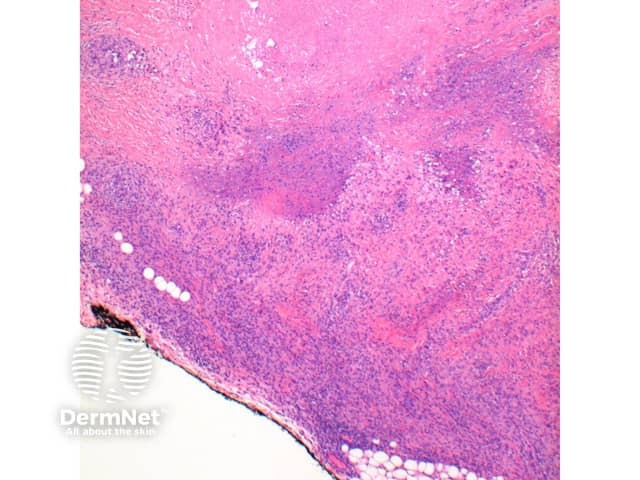

The scanning view of the histology of granuloma annulare shows a granulomatous inflammatory pattern situated within the superficial and mid dermis.

Figure 1